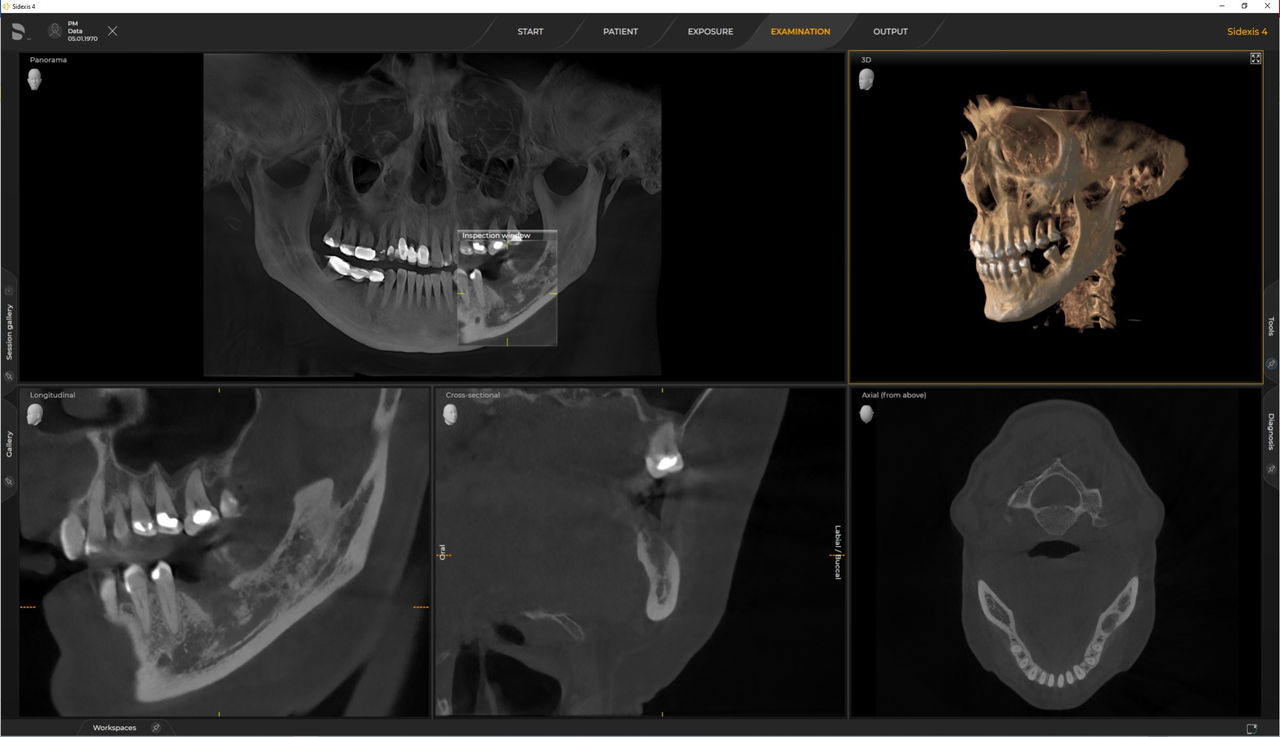

Dentsply Sirona 3D units work exclusively with Sidexis 4. Nevertheless data migration from Sidexis XG to Sidexis 4 is very easy. Sidexis 4 allows for the full digital experience with the latest tools.